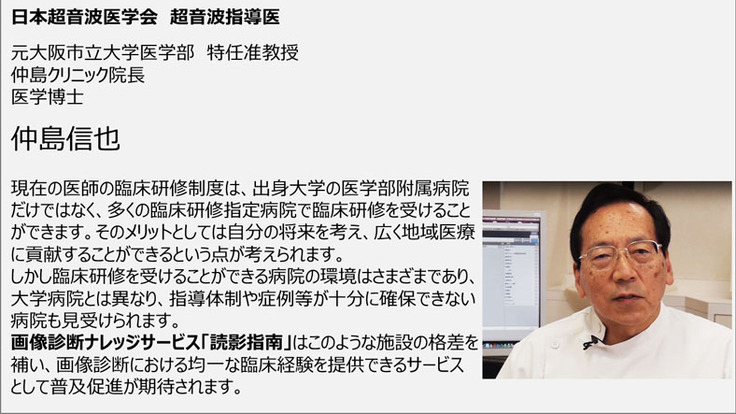

診断精度の「ばらつき」が社会問題となっている画像診断については、大阪大学、大阪市立大学、関西医科大学など大学病院に所属する胸部X線、腹部超音波、内視鏡などの「専門医」「指導医」の先生方、知識情報処理(AI)の研究者・技術者が、大学病院や企業と協働して臨床現場における画像診断の精度向上をサポートするサービスの開発を行っています。

その成果を利用して開発したメディカル指南車の”画像診断ナレッジサービス「読影指南」”は、「専門医」以外の医師や診療放射線技師に対して効率的に画像診断の精度向上をサポートできるサービスを提供します(下図)。画像診断ナレッジサービス「読影指南」は、単に特定の疾患の症例を理解するだけではなく、体系的に画像診断を理解して臨床現場で応用することができるこれまでにないサービスです。

現在、”画像診断ナレッジサービス「読影指南」”は画像診断の精度向上に対する優位性が認められ、採用施設が増えつつあります。すでに”画像診断ナレッジサービス「読影指南」”を導入している兵庫県立加古川医療センターでは、研修医の臨床経験を補う目的でご利用いただいています。一方、診療放射線技師を養成している鈴鹿医療科学大学では、3,4年生全員が”画像診断ナレッジサービス「読影指南」”を用いて学習しています。このように既に医師や技師の育成にお使いいただいている施設では大変好評をいただいていますが、この機会に多くの医療機関などに”画像診断ナレッジサービス「読影指南」”を提供して、ひとりでも多くの医師や診療放射線技師の臨床経験を補うことにより画像診断の精度向上に役立てていきたいと考えています。その結果、疾患の早期発見により、患者やその家族の肉体的、経済的、さらには精神的な負担軽減に貢献することがメディカル指南車の願いです。